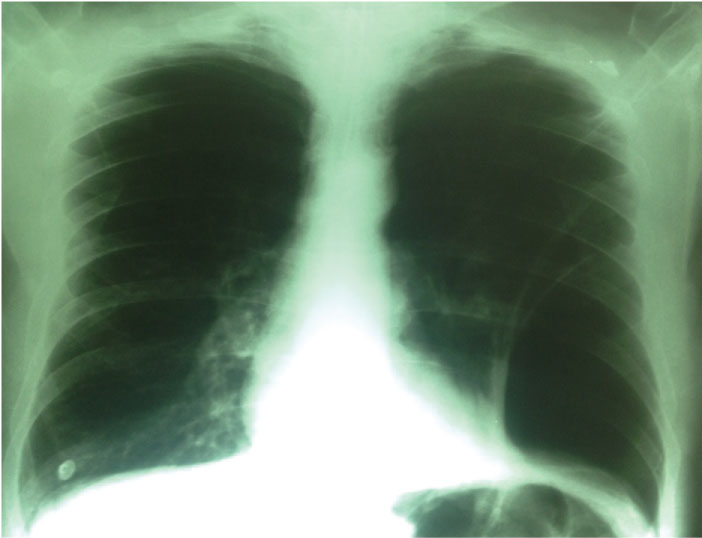

In the last radiograph, pleural drainage tube was observed with the disappearance of the image of absence of arborization in the lower left field observed at its entrance (Figure 7).

Figure 7: Pleural drainage tube with the disappearance of the image of absence of arborization in the lower left field observed at its entrance.